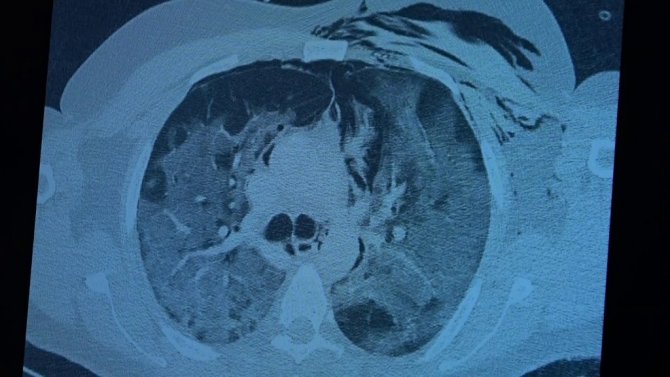

Covid-19 servisinde yatan hastaların yüzde 80'inin gençlerden oluştuğunun altını çizen Prof. Dr. Özkaya, "Artık daha genç hastaların mutant virüsle karşılaştıkları için daha ağır geçirdiği görüyoruz. 60 ve 65 yaş üstünü ise aşıyla sigortaladığımızı düşünüyoruz. Aşının gerçek yaşam sonuçlarının olumlu olduğunu görüyoruz. Aşı olanlar virüse yakalandıkları halde çok hafif veya hastaneye yatmadan atlatıyorlar. Şu an servisimizde yatan hastaların yüzde 80'inini genç hastalar oluşturuyor. Artık 60 yaş üstünde çok fazla hasta görmüyoruz. Örneğin (akciğer filmini gördüğümüz) 40 yaşındaki bir hastamız aşılanmadığı için mutant virüse yakalanmış. Akciğerleri çok kötü durumda ve hastanede yatıyor. 24 yaşında bir genç kızımızda ise ciddi akciğer tutulumları görüyoruz. 49 yaşında bir hastamızı ise maalesef çok ciddi akciğer tutulumu ve neredeyse paramparça bir akciğerle yoğun bakımda takip ediyoruz" şeklinde konuştu.